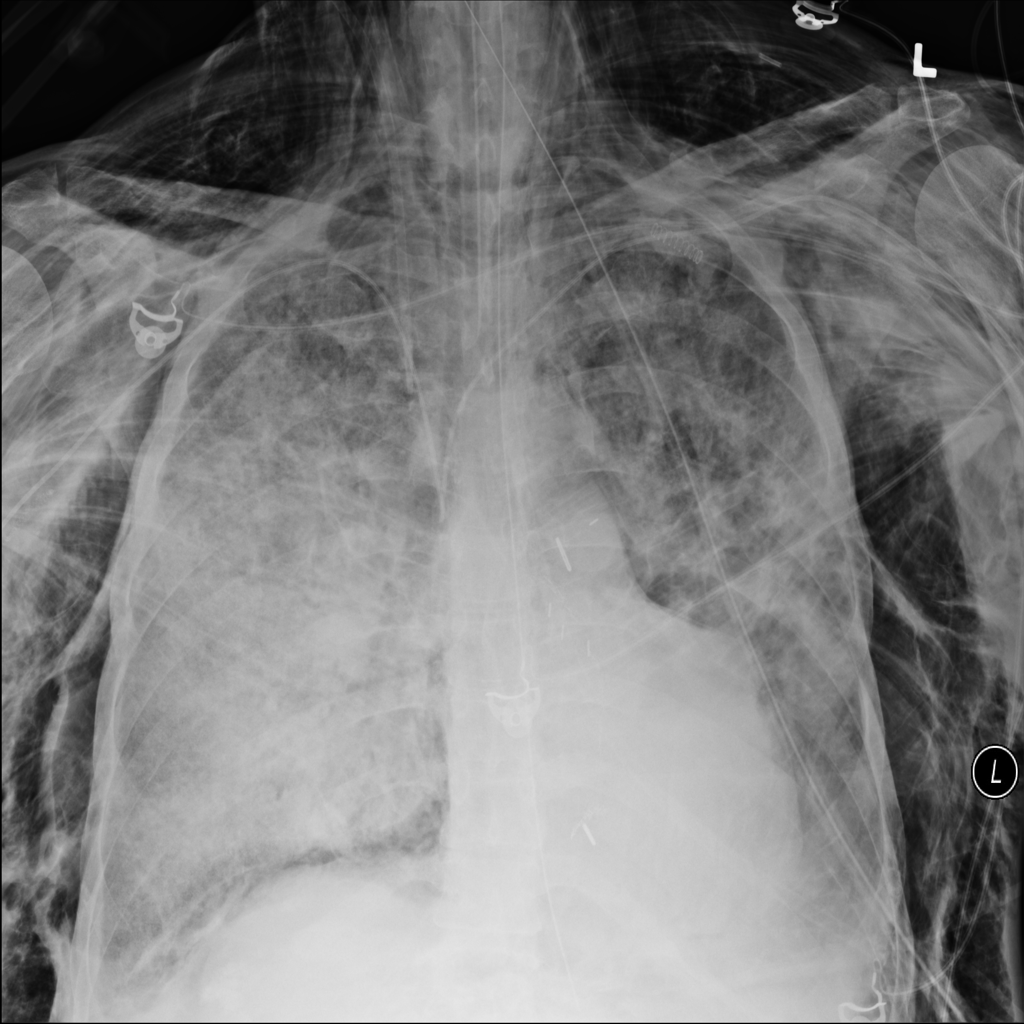

PAT-4639 · IMG-020Pneumothorax

PAT-4639 · IMG-020

PA